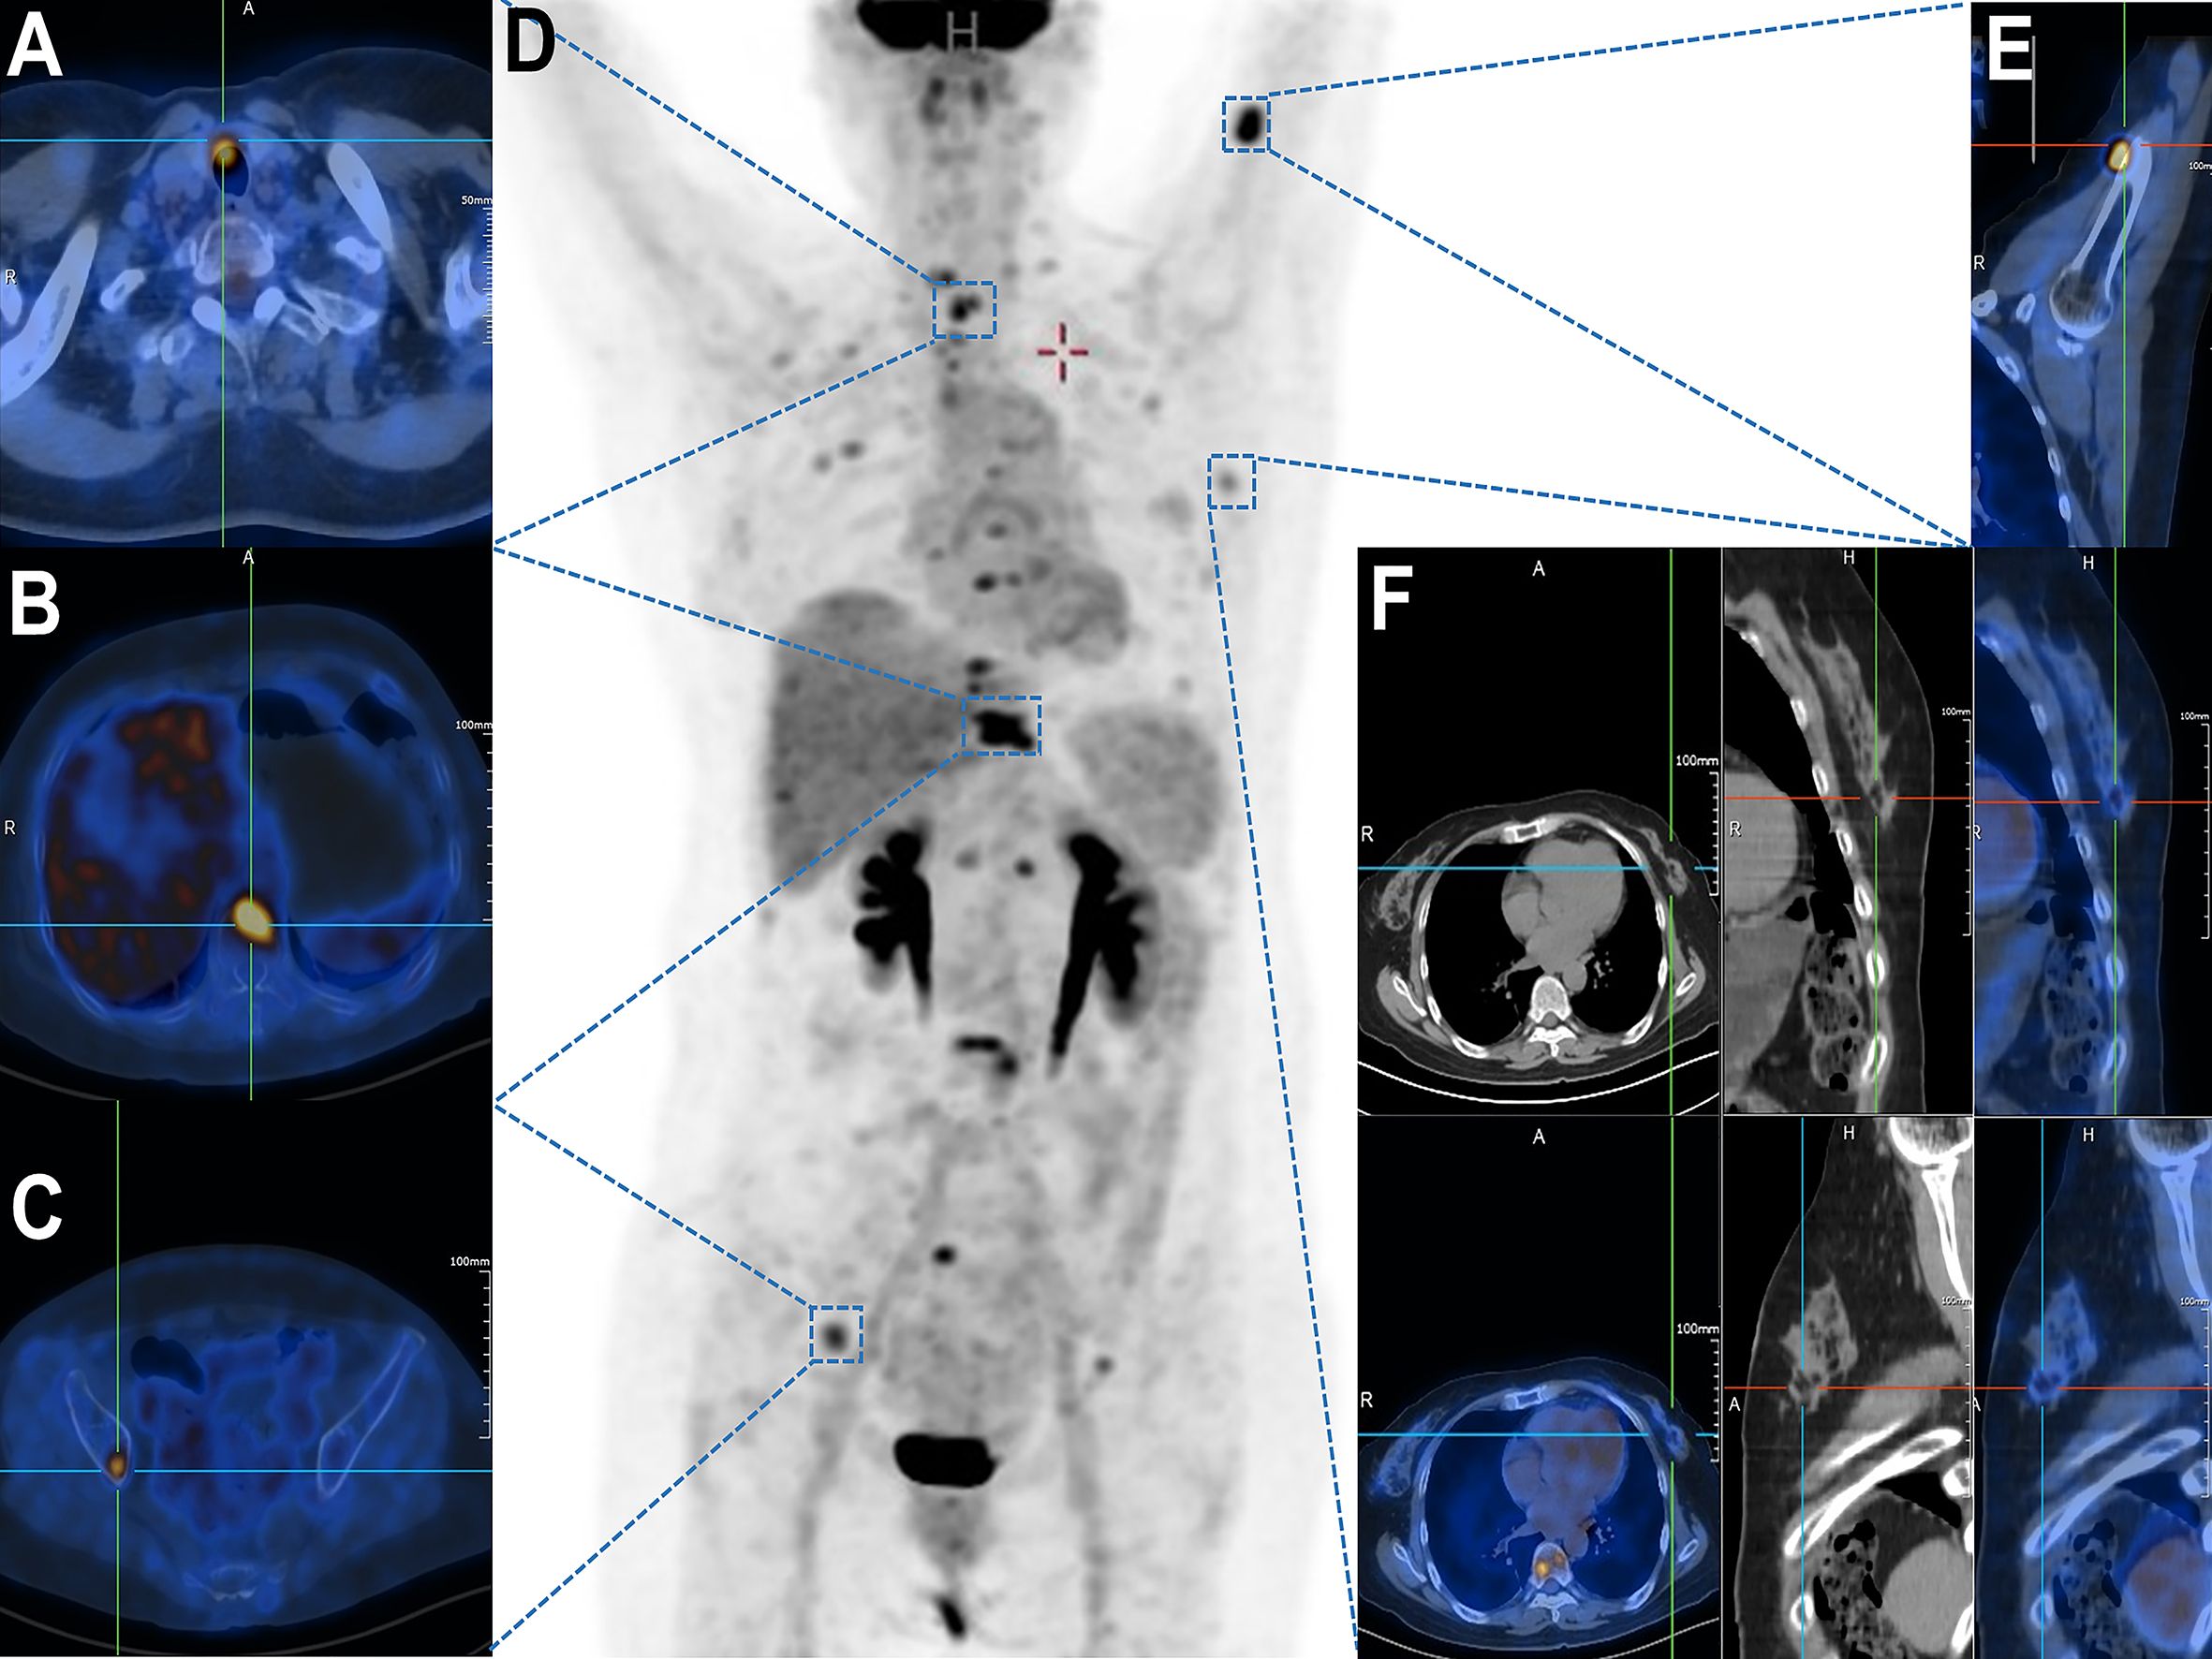

18F-FDG PET/CT (Figure 1D) demonstrated a highly metabolic right thyroid nodule (13.0 × 6.7mm, SUVmax 9.41; Figure 1A) alongside FDG-avid lymphadenopathy in submandibular/cervical/supraclavicular (SUVmax 2.58) and mediastinal regions (SUVmax 4.19). Extensive hypermetabolic bone metastases were evident, including a pathological T10 fracture (SUVmax 11.64, CT HU 876; Figure 1B), right iliac lesion (SUVmax 6.32; Figure 1C), and left proximal humeral lesion (SUVmax 11.47; Figure 1E). A left breast nodule showed only borderline FDG uptake (SUVmax 2.19; Figure 1F), subsequently confirmed as benign (BI-RADS II) with periareolar fibrosis on ultrasound, consistent with chronic mastitis.

Composite of medical imaging scans displaying various perspectives. Panel A shows a PET/CT scan of the abdomen cross-section highlighting metabolic activity. Panel B displays a PET/CT scan of a thoracic cross-section. Panel C shows a PET/CT scan of the pelvic region. Panel D depicts a full-body scan with focus points marked. Panel E highlights the sagittal view of a specific region. Panel F is a series of cross-sectional, sagittal, and coronal images of the chest, showcasing anatomical structures and metabolic regions.

Figure 1. Whole-body 18F-FDG PET/CT demonstrating multifocal hypermetabolic lesions. (A) Thyroid isthmus lesion with focally increased FDG uptake (SUVmax = 9.41). (B) Vertebral metastasis at T10 level (SUVmax = 11.64). (C) Right iliac bone lesion showing elevated metabolic activity (SUVmax = [value]). (D) Maximum intensity projection (MIP) image revealing systemic dissemination of metabolically active metastases. (E) Left proximal humeral lesion with abnormal FDG avidity (SUVmax = [value]). (F) A suspicious mass in the left breast upper-outer quadrant demonstrated focal FDG avidity (SUVmax = 2.19) on axial, coronal, and sagittal fused PET/CT views.